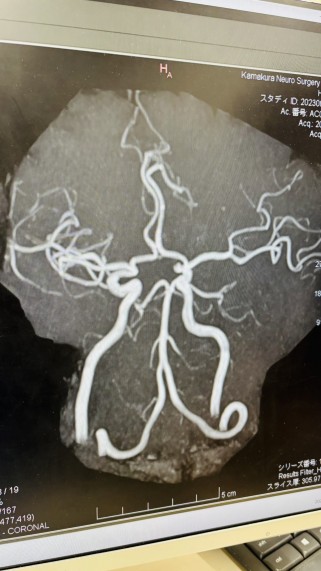

MRIなどの検査をしてもらった結果――

「脳と血管、年齢のわりにめちゃくちゃキレイですよ!」とお墨付きをいただきました!